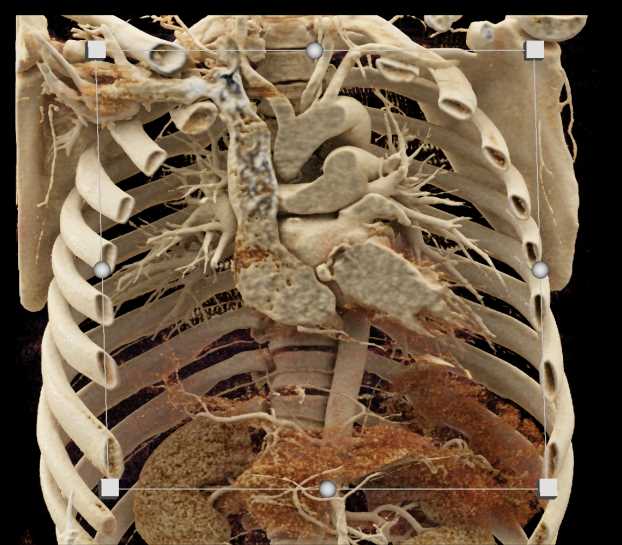

Aortic Valve Repair